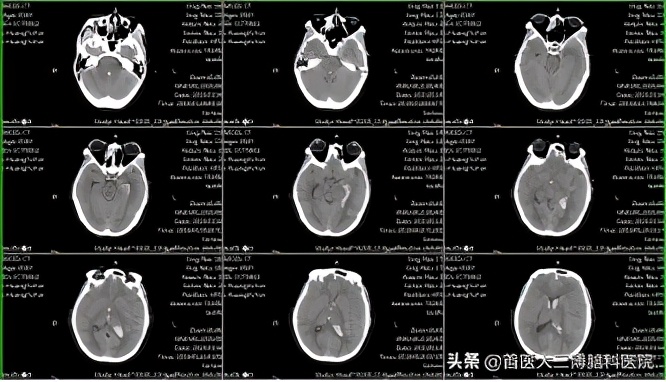

妊娠27周孕妇突发脑出血多学科协作紧急救治 首医大三博脑科医院 Mdeditor